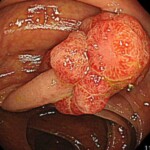

@便潜血検査陽性で大腸カメラを受けて日帰り切除できた大腸腺腫